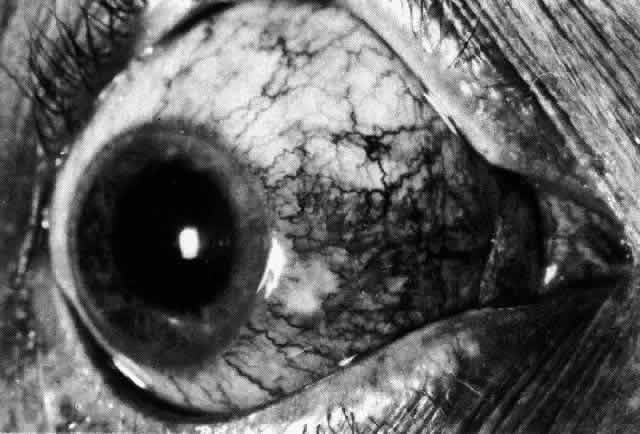

Necrotizing anterior scleritis without adjacent inflammation appears to be a well-defined condition with little relation in clinical features to necrotizing scleral disease, even though the pathology is similar and the final result is the same. Scleromalacia perforans is characterized by the almost total lack of any symptoms. It occurs almost exclusively in patients with long-standing polyarticular rheumatoid arthritis, the majority of whom are female (Figs. 49 and 50; Color Plate 1E).

The anterior sclera loses its covering of episclera and develops an area of yellow-white necrotic slough over many months; this eventually separates or is absorbed, leaving the underlying choroid covered by either conjunctiva or nothing at all. As with necrotizing disease, the choroid does not bulge into this ectatic area; but unlike necrotizing disease, spontaneous healing of even small perforations is very limited once the necrotic tissue has been removed (see Fig. 50).

Fluorescein angiography is not helpful, except to indicate areas of vascular closure in an otherwise extremely thin, atrophic episcleral tissue.4 The formation of a sequestrum appears to be caused by arteriolar closure as opposed to the venular disease seen in the other forms of necrotizing scleritis.